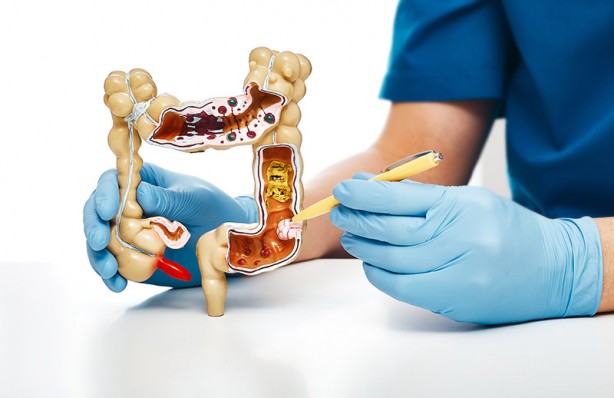

Bağırsak tıkanıklığı veya bir diğer adıyla bağırsak düğümlenmesi ince bağırsakta veya kalın bağırsakta gıda ve sıvıların geçmesine izin vermeyen bir tıkanıklık meydana gelmesidir.

Bağırsak tıkanıklığı türleri İki tür bağırsak tıkanıklığı vardır. Bağırsaklar tıkanma yoluyla mekanik olarak veya hareketsizlik yoluyla paralitik olarak bloke olabilir. Mekanik tıkanıklık sırasında, bağırsaklardaki bazı fiziksel engeller nedeniyle dışkı hareket edemez. Bu gibi durumlarda, engeli kaldırmak genellikle sorunu çözer. Paralitik bağırsak tıkanıklığı durumunda mekanik tıkanıklık yoktur. Bu gibi durumlarda sinir veya düz kas problemlerinden dolayı bağırsak hareketi durduğu için bağırsak içeriği bağırsaklarda hareket edemez. Sonuç olarak, bağırsaklardaki yiyecek ve sıvılar hareket edemez, bu nedenle tıkanıklık kısa sürede gelişir.

-Mekanik bağırsak tıkanıklığının nedenleri- Mekanik nedenler, esas olarak bağırsakların daralması veya bir tür tıkanma nedeniyle olabilir. Mekanik bağırsak tıkanıklığının birçok nedeni vardır. Bunlardan en yaygın olanları şunlardır: -Bağırsak yapışıklıkları- Bu durumda karın boşluğundaki lifli dokular bağırsakların birbirine yapışmasına neden olur. Yapışıklıklar en sık abdominal veya pelvik cerrahiden sonra ortaya çıkabilir. -Kolon kanseri- Kolon kanseri, kolon tıkanıklığının yaygın bir nedenidir. Kanserli tümörün büyümesi nedeniyle, kolon daralır ve aynı zamanda bloke olur. Tıkanma genellikle yavaş yavaş, önce kabızlık ve daha sonra tam tıkanıklık olarak gelişir.